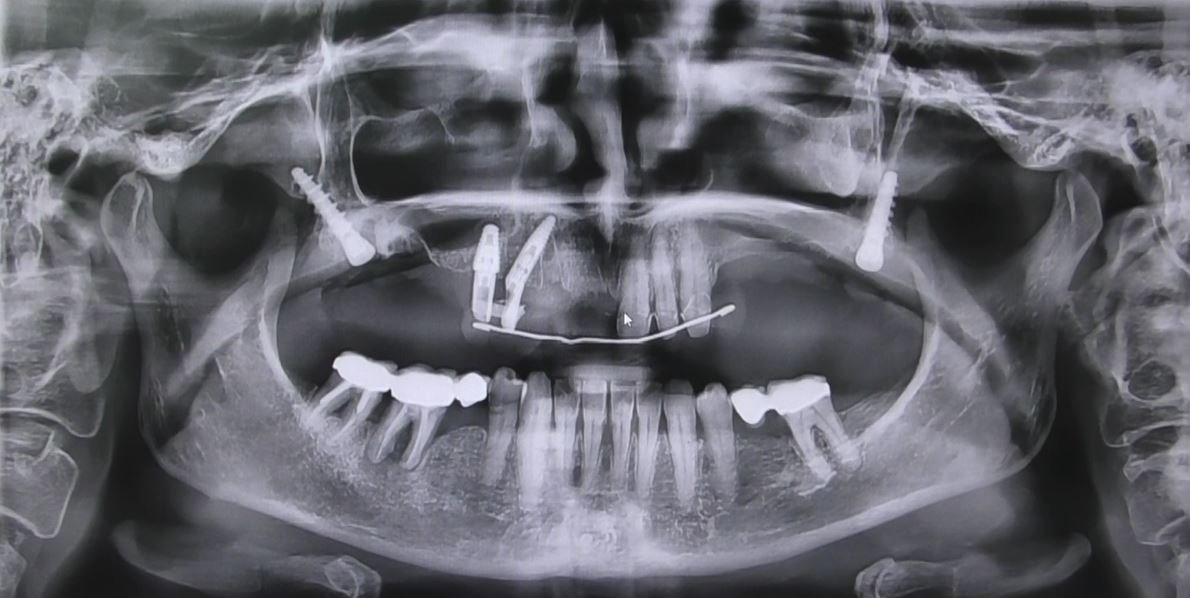

- Valutazione Radiografica: Una valutazione dettagliata ha fornito informazioni cruciali sulla quantità di osso disponibile e sulla strategia di posizionamento degli impianti.

- Posizionamento degli Impianti Sottoperiostei: Gli impianti sono stati posizionati direttamente sulla superficie dell’osso mascellare, garantendo stabilità e supporto adeguati.

Il nostro paziente, affetto da grave atrofia ossea mascellare, è stato selezionato per sottoporsi a questa procedura avanzata. La valutazione preoperatoria accurata ha guidato la pianificazione, assicurando che la tecnica fosse adattata alle specifiche esigenze anatomiche del paziente.